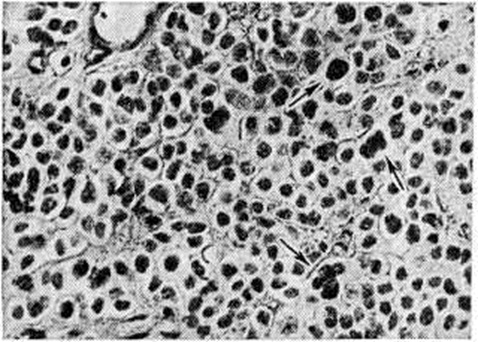

Микроскопически различают Олигодендроглиома типической и атипической структуры. Типические Олигодендроглиома состоят из густо и равномерно расположенных клеток со скудной цитоплазмой и ядрами сферической формы с нежными глыбками хроматина и чётким ядрышком (рисунок 2), напоминающих обычный олигодендроглиоцит. Нередко ткань опухоли приобретает мелкоячеистую (напоминающую соты) структуру, в центре ячейки располагается по нескольку ядер, окружённых светлой неокрашенной зоной (рисунок 3). Иногда в ткани Олигодендроглиома наряду с клетками, напоминающими олигодендроглиоциты, обнаруживают пучки веретенообразных клеток с отростками и ядрами вытянутой формы. В ряде случаев в Олигодендроглиома встречаются участки астроцитомы (смотри полный свод знаний), которая содержит глиальные волокна, импрегнирующиеся методом Рамон-и-Кахаля. Подобные опухоли диагностируются как олигодендроастроцитомы.. В Олигодендроглиома имеется небольшое или умеренное количество мелких сосудов. Характерным является отложение солей извести в ткани опухоли, сосудах и прилежащем мозговом веществе. Нередки мелкие кисты.